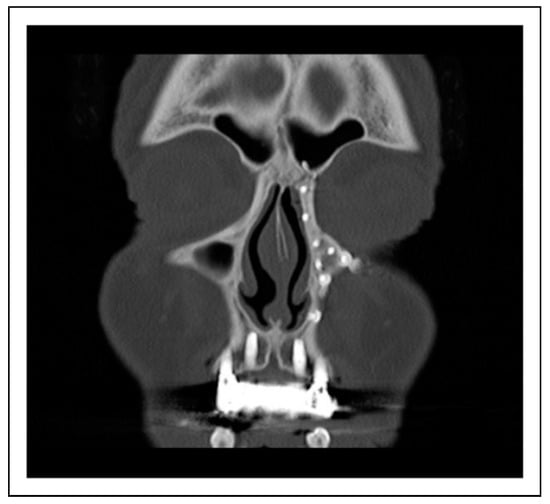

Endoscopic Dacryocystorhinostomy Following Nasolacrimal Drainage System Trauma and Medial Orbital Wall Reconstruction

Case 1

Case 2